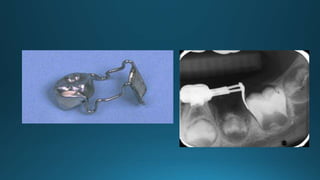

Band and loop space maintainers

Crown & loop appliance

Preformed bonded space

maintainer